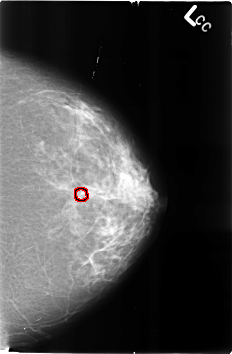

B_3247_1.LEFT_CC

LEFT_CC LINES 4592 PIXELS_PER_LINE 3016 BITS_PER_PIXEL 12 RESOLUTION 50 OVERLAY

FILE: B_3247_1.LEFT_CC.OVERLAY

TOTAL_ABNORMALITIES 1

ABNORMALITY 1

LESION_TYPE CALCIFICATION TYPE LUCENT_CENTER DISTRIBUTION N/A

ASSESSMENT 2

SUBTLETY 3

PATHOLOGY BENIGN_WITHOUT_CALLBACK

TOTAL_OUTLINES 1

BOUNDARY